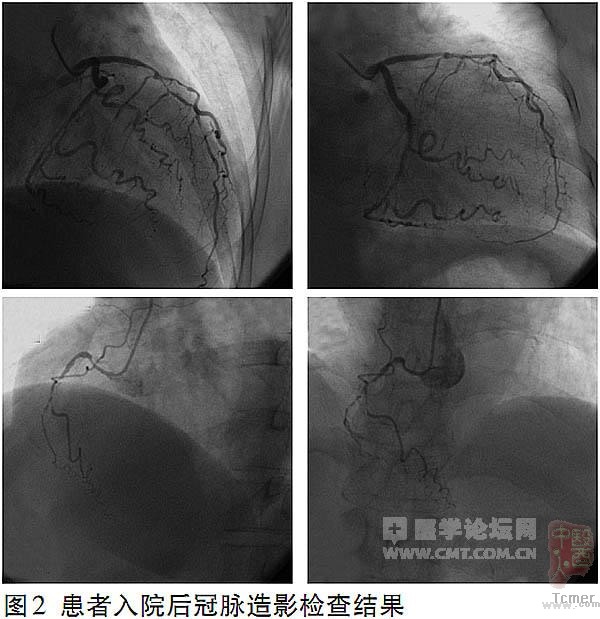

冠状动脉造影 血管情况较差,存在3支病变(图2),未行经皮冠状动脉介入术(PCI)。